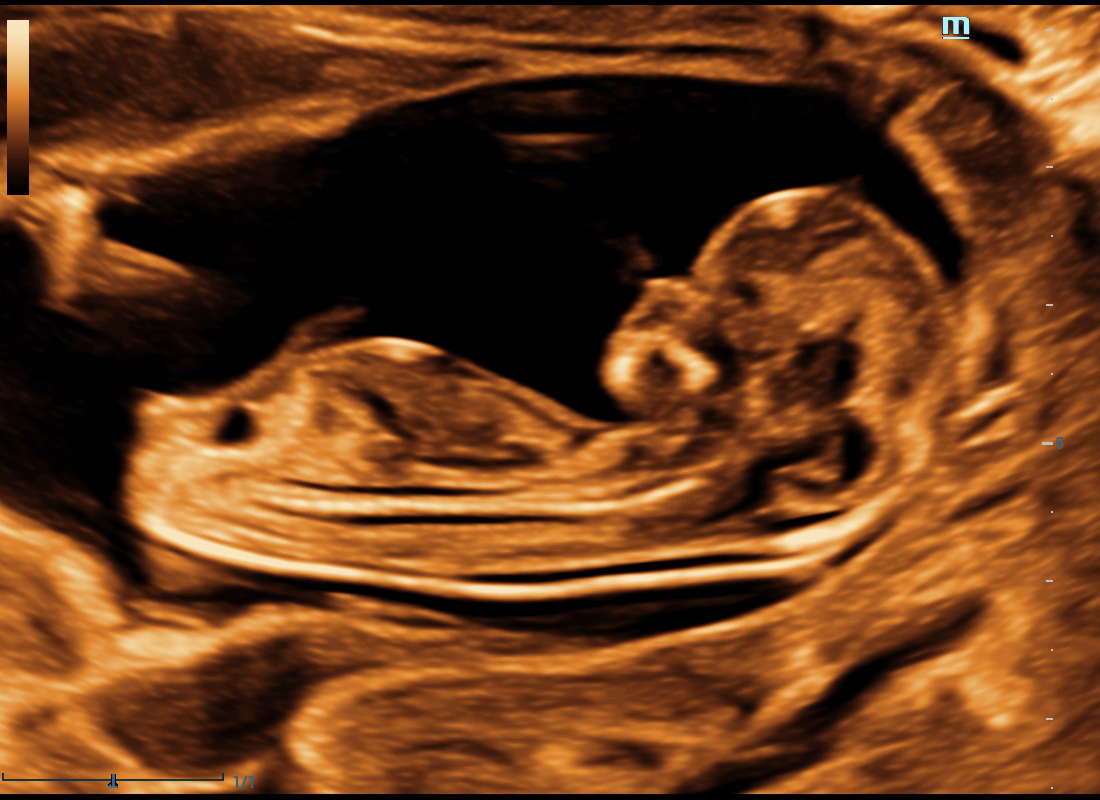

The volume imaging of fetal face is very important for the obstetric doctors whehere they make the face malformation diagnosis or a fully communication with parents. We deeply understand how Nuewa users need more intuitive fetal stereoscopic imaging to help parents quickly establish parent-child links at different gestational weeks.

Thanks to Dr. Amr Salsh, Wadil Elnil Radiology Center, Egypt